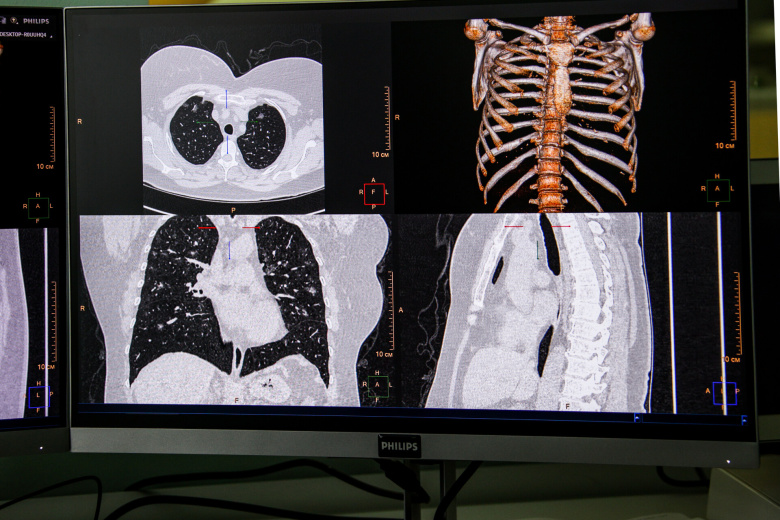

Фото: Сергей Лантюхов/NEWS.ru